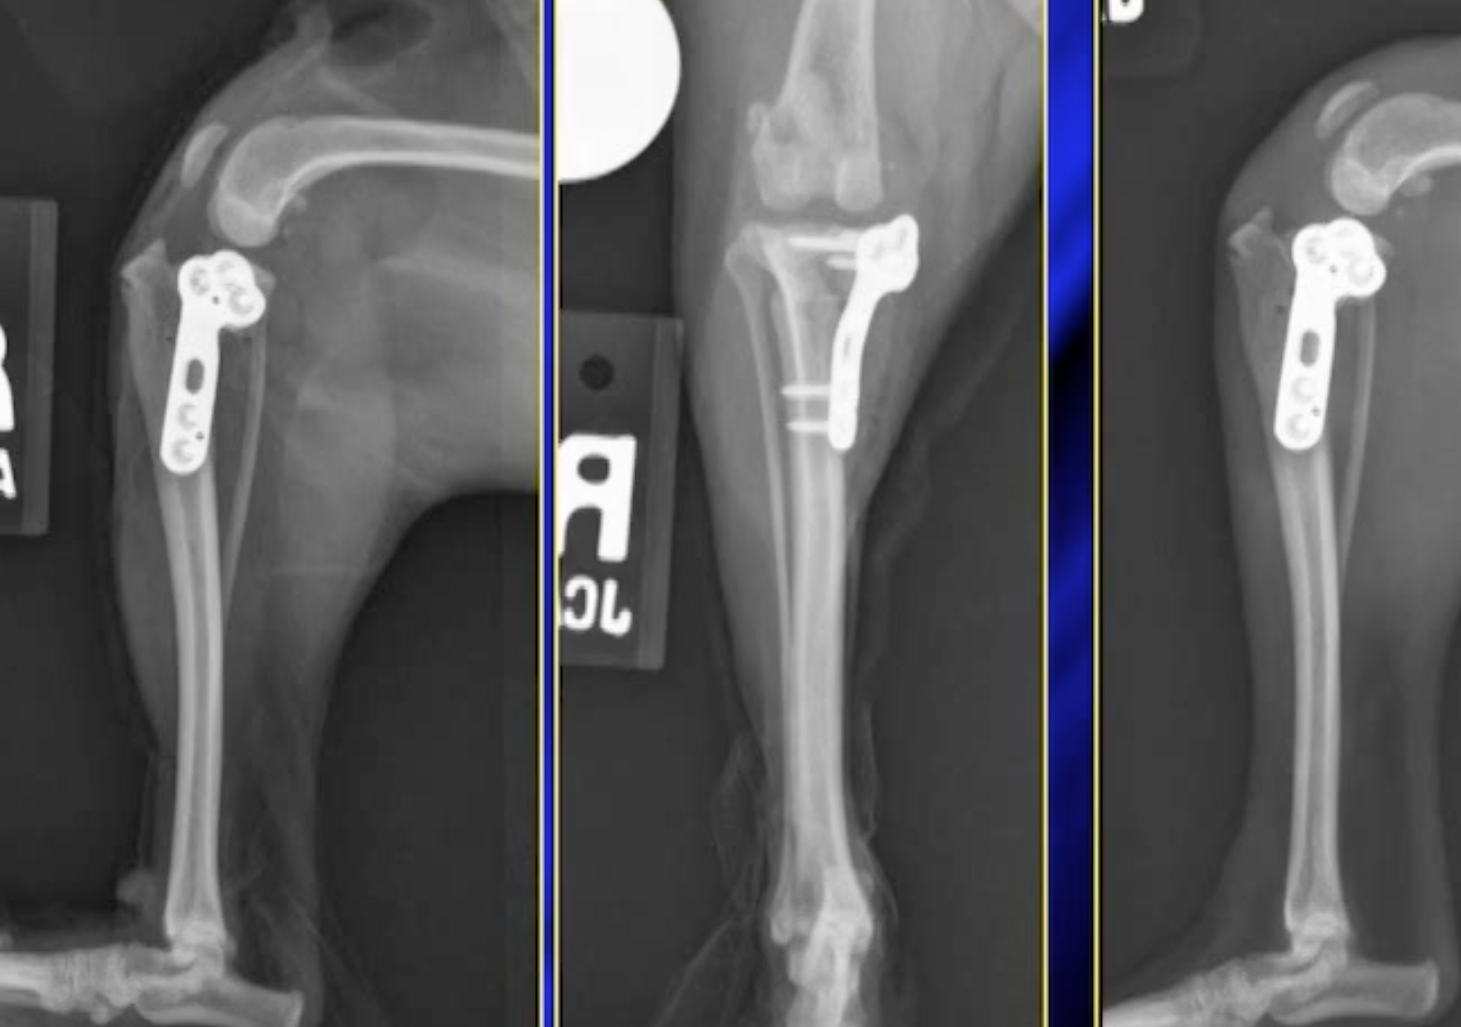

Médiale de la rotule luxation est une commune du développement orthopédique anomalie qui provoque souvent de la boiterie chez les chiens. Alors que le diagnostic de la médial de la rotule luxation est simple, la mise en œuvre de traitement est plus cérébral. La décision de traiter et si oui, quelles sont les options devraient être mises en œuvre sont essentiels pour un résultat optimal, en particulier chez les chiens atteints de grade supérieur luxations ou simultanées du ligament croisé crânial de l'insuffisance. Cette conférence abordera l'état actuel de la gestion de médial luxation patellaire.